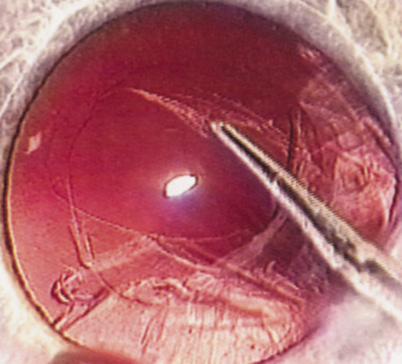

ANTERIOR CAPSULOTOMY

One of the most beneficial techniques developed over the last decade is capsulorrhexis. A continuous curvilinear anterior capsular opening helps prevent intraoperative and postoperative complications. With capsulorrhexis, mechanical strength of the capsular opening is superior to that in a can-opener capsulotomy; thus, a tear to the posterior capsule with subsequent vitreous loss is much less likely.96 Capsulorrhexis allows for nuclear manipulation with less risk of posterior capsule rupture. Cortex removal is made easier as well, because it becomes easier to differentiate cortical material from anterior capsule. Should a posterior capsular tear occur, sulcus fixation is more likely attainable with the presence of a clearly visible residual anterior capsular rim. Placement of both IOL haptics into the capsular bag is more certain with capsulorrhexis because the surgeon can more easily visualize the haptics gliding beneath the anterior capsular rim.

Capsulorrhexis can be performed with a cystitome, capsulorrhexis forceps, or combination-type instruments. Regardless of which instrument is used, several principles can help the surgeon successfully complete capsulorrhexis. It is important to maintain the anterior chamber, because making the chamber shallow increases tension on the zonules and causes the tear to run peripherally. The authors recommend the use of a viscoelastic agent for maintaining chamber depth and, of course, for endothelial protection. Therefore, if the tear begins to run peripherally, the surgeon should redeepen the anterior chamber before attempting to redirect the tear. Additionally, folding the capsule margin can aid the surgeon in redirecting the tear more accurately (Fig. 10).

Fig. 10. The capsulorrhexis tear is more easily redirected by folding the capsule over, in advance of the tear.